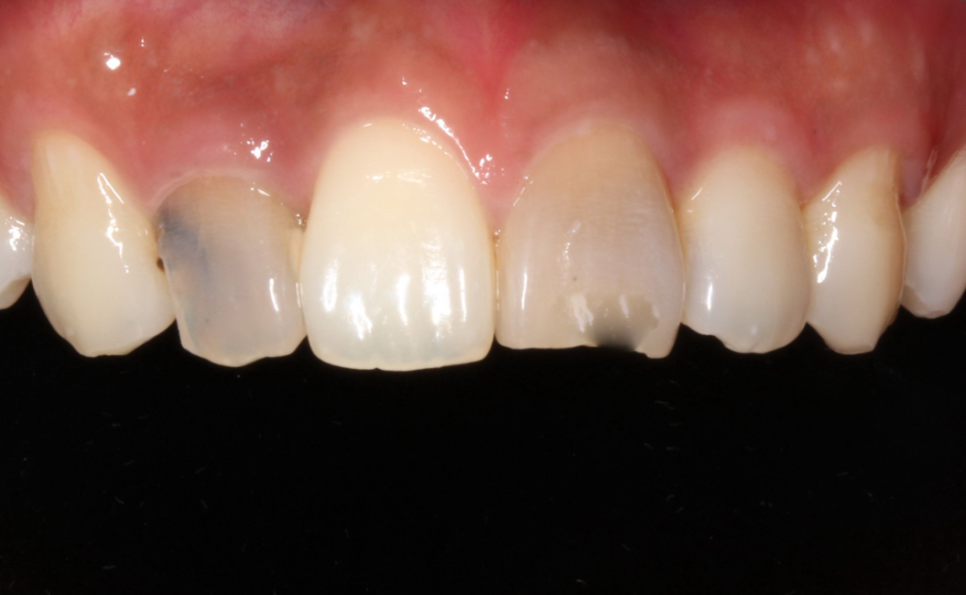

BEFORE

AFTER

앞니깨짐과 같은 상황이 발생하게되면 치아를 상대방에게 보여주지 않기 위해 입을 가리고 웃거나 말을 할때도 발음이 이상해지는 등 다양한 문제가 생길 수 있답니다.

누군가의 얼굴을 마주했을 때 첫 이미지를 결정짓는 요소로 작용하는 치아 그리고 미소. 앞니는 심미성에서 큰 역활을 하기 때문에 문제가 생긴 경우에는 빠른 치료를 진행하는 것이 좋습니다(✿◡‿◡)